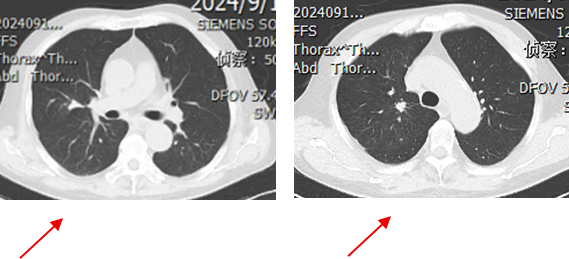

一线第2周期治疗后及4周期治疗后(2024-07-16上2024-09-11下)

1.png

2.png